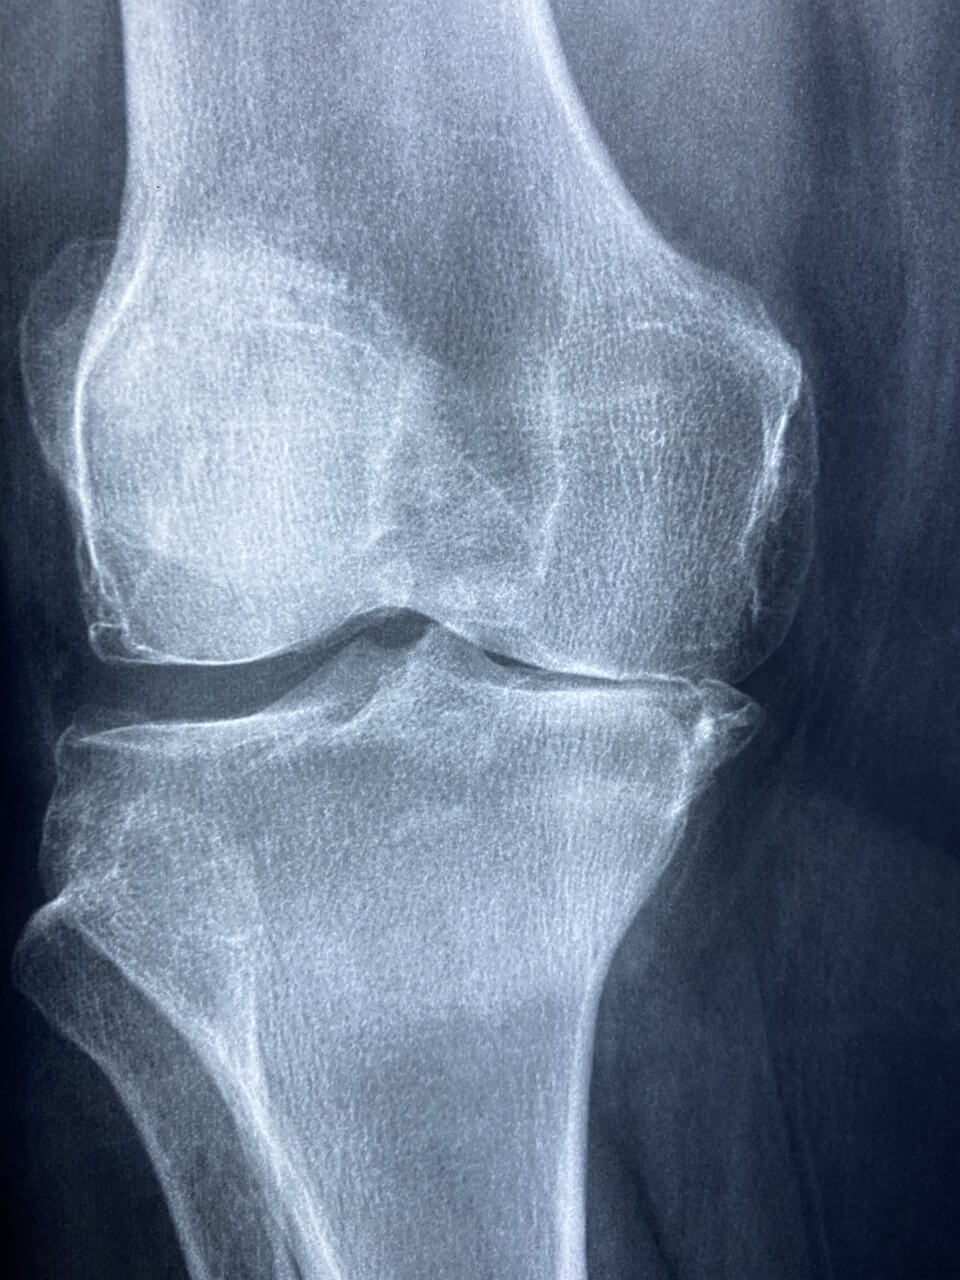

골다공증 초기증상은 눈에 잘 띄지 않아 많은 이들이 놓치기 쉽습니다. 뼈는 겉으로 드러나지 않지만 조용히 약해지고 있습니다. 사소한 허리 통증이나 무릎 불편감도 골다공증 초기증상일 수 있습니다.

골다공증 초기증상은 일상 속 사소한 불편으로 나타납니다. 무릎이 시큰거리거나 오래 서 있기가 힘들고, 이전보다 허리가 자주 아프다면 뼈 건강을 의심해봐야 합니다.

골다공증 초기증상이 계속된다면 반드시 전문의를 찾아 정확한 골밀도 검사를 받아야 합니다. 정기적인 검사는 뼈 상태를 객관적으로 파악할 수 있는 가장 좋은 방법입니다.